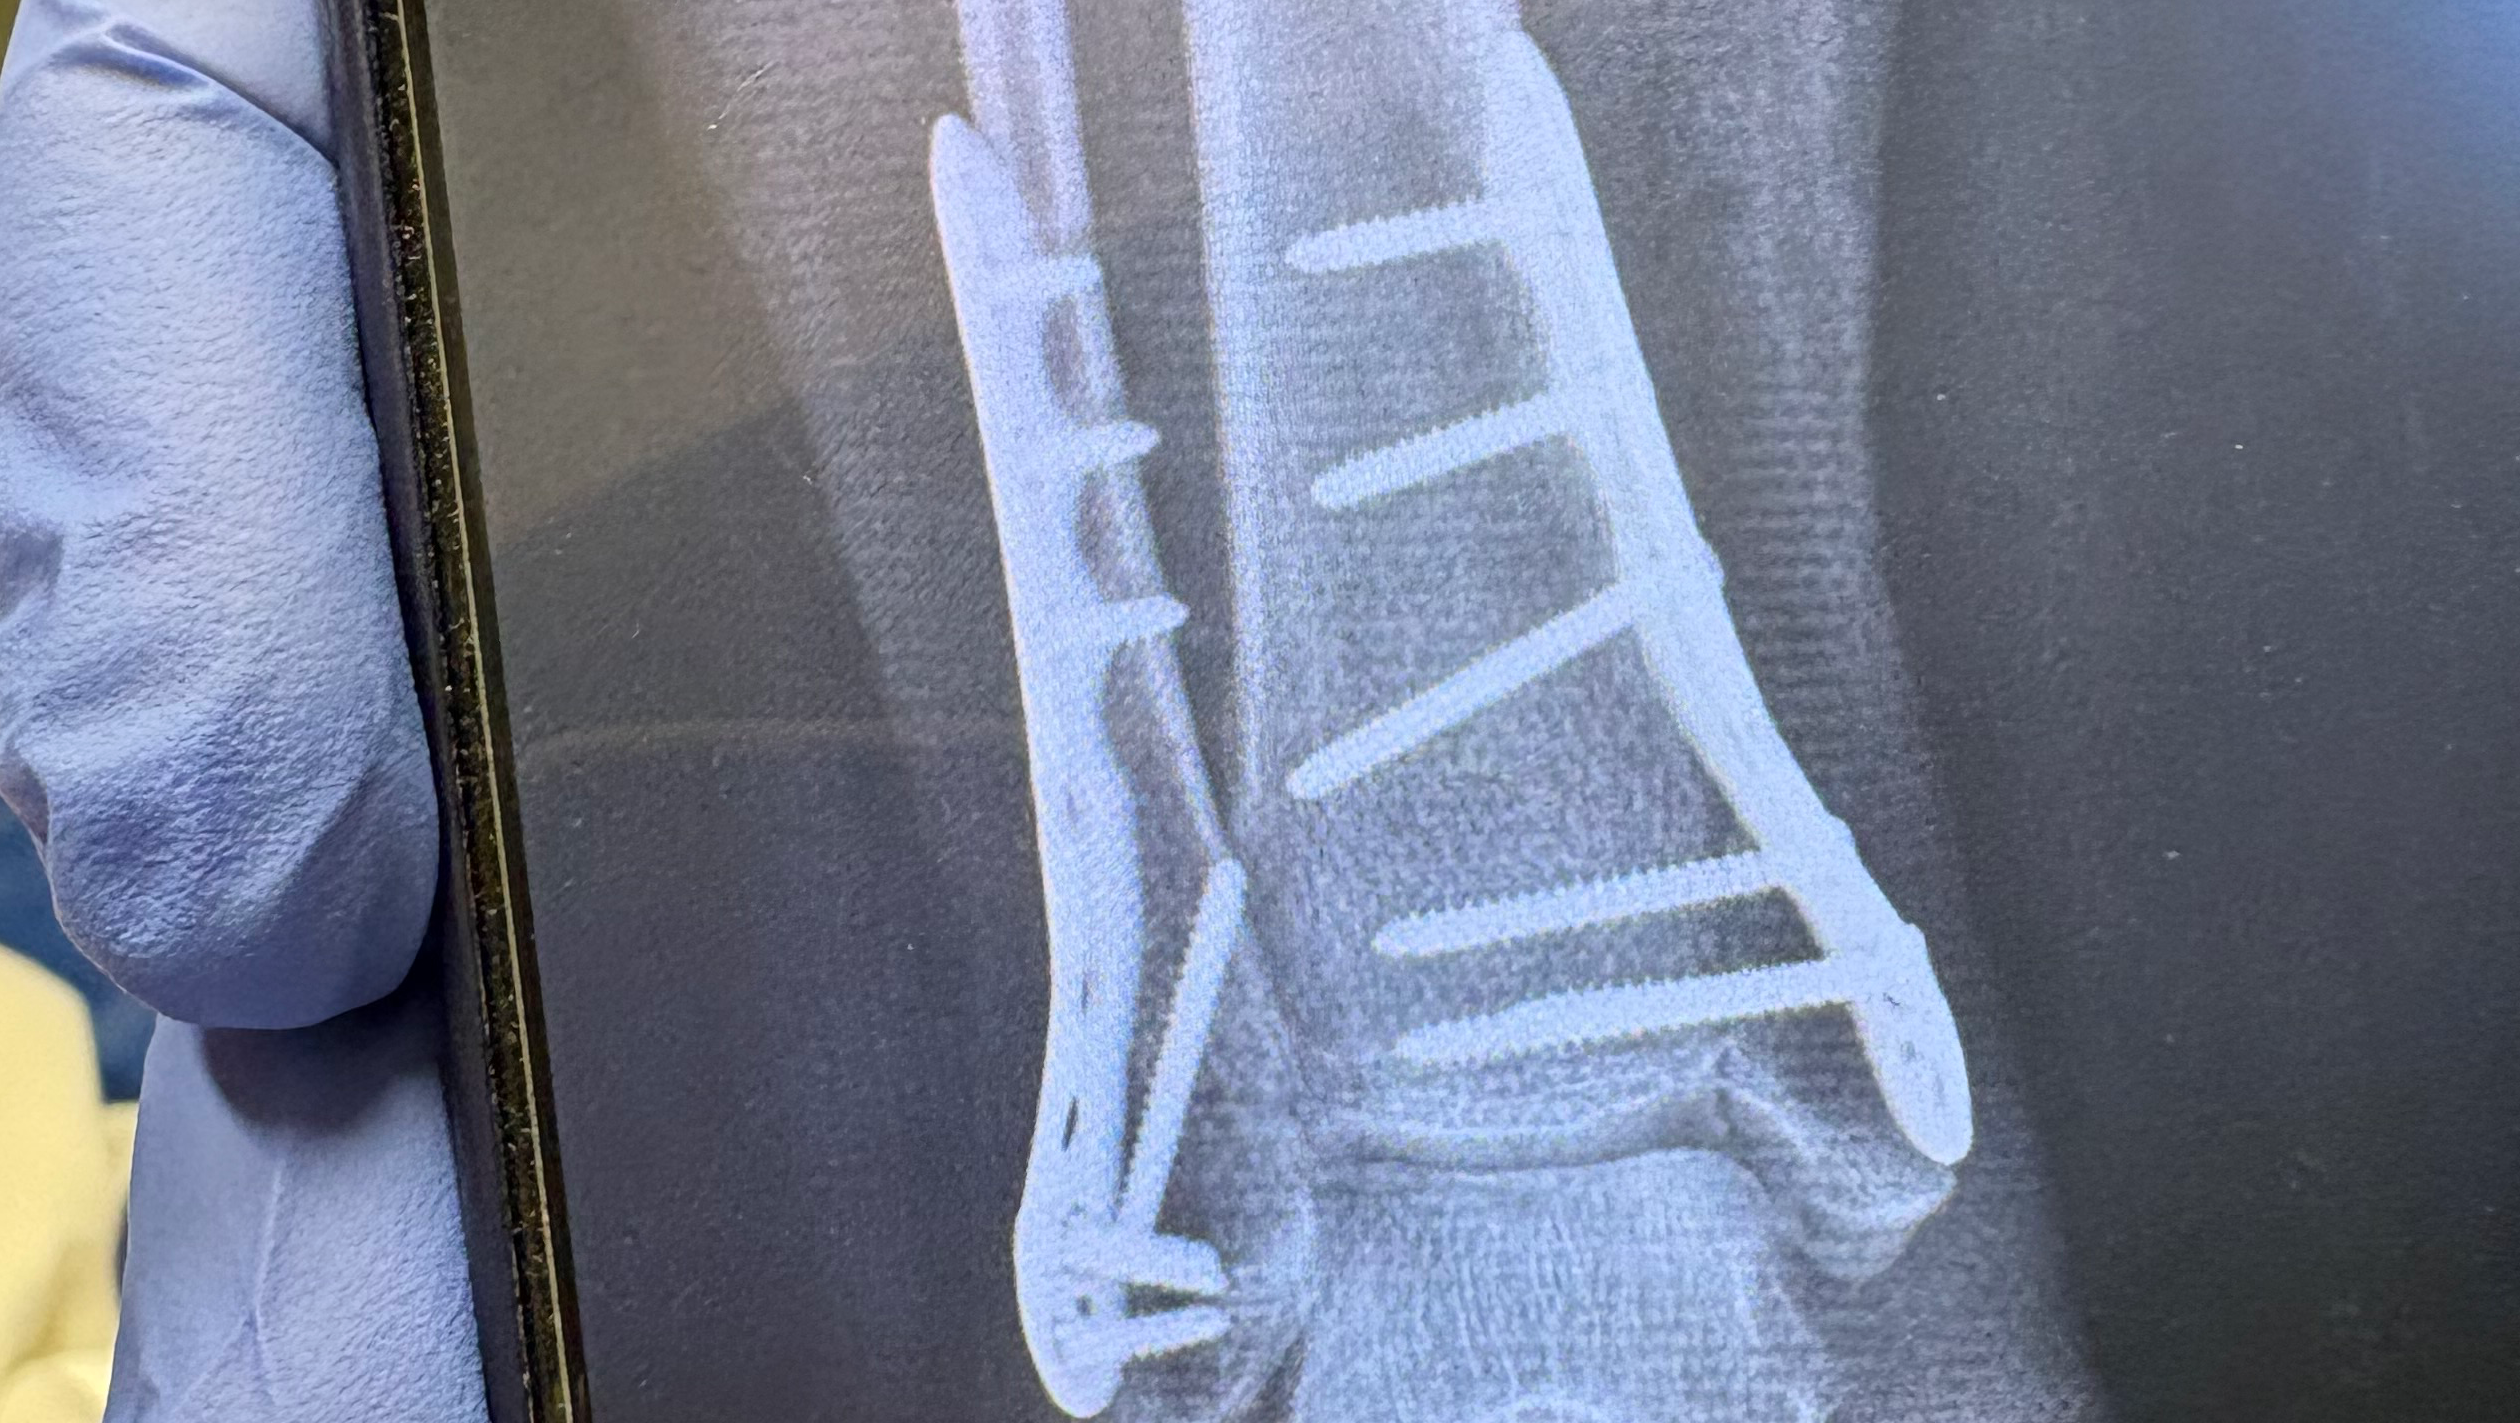

My name is Monica, and I'm a single mom of three wonderful kids. Recently, I experienced a life-changing accident when I jumped off my horse and broke every bone in my ankle. The injury was so severe that I needed surgery, which resulted in 13 screws and 2 plates being put into my ankle. The recovery process is long and challenging, and it's turned my world upside down. Because of this injury, I am unable to work for the next 12 to 16 weeks and can’t do any of the side jobs I usually rely on to support my family. As the sole provider, being out of work is costing us the things we need most. The medical bills are already piling up, and I’m also facing extra costs for supplies, household essentials, and making sure my kids are taken care of while I recover. I’m reaching out for help to cover rent, medical expenses, and the everyday needs that keep our family going. Any support—whether it’s a donation or simply sharing my story—would mean the world to us. Thank you for taking the time to read about our situation and for considering helping my family during this difficult time.